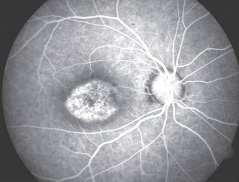

• Transmitted fluorescence is also called a "window defect."

• Healthy RPE usually block fluorescence from the choroidal vasculature, meaning RPE defects will result in choroidal hyperfluorescence. This may be caused by atrophy of the RPE layer or a congenital reduction in the pigment epithelium.

• Hyperfluorescence occurs in the same shape as the RPE defect and does not increase in size or shape with time. This window defect fades as the dye washes out of choroidal circulation.

• Usually this is caused by a pigment epithelial window defect.

• Atrophy of pigment epithelium.

• Congenital reduction in pigment epithelium.